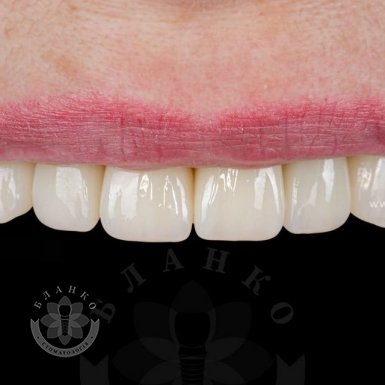

Зубна імплантація — це сучасне та надійне рішення для відновлення втрачених зубів. У стоматологічній клініці Бланко ми пропонуємо імплантацію зубів «під ключ», що означає повний комплекс послуг — від діагностики до встановлення коронки, без прихованих платежів та несподіваних витрат.